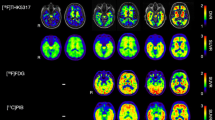

Comparison of [18F]flortaucipir (FTP) and [18F]RO948 parametric BPND (Logan DVR-1) images (a, c) and regional SUV, SUVR, and SUVR vs DVR data (b, d) in two cases with AD dementia with high tau burden. Stage I/II, entorhinal cortex; stage III/IV, temporal/limbic cortex; stage V/VI, neocortex. CP, choroid plexus; BG, basal ganglia; FTP, Flortaucipir; ITC, inferior temporal cortex

Comparison of [18F]flortaucipir (FTP) and [18F]RO948 parametric BPND (Logan DVR-1) images (a, c) and regional SUV, SUVR, and SUVR vs DVR data (b, d) in two cases with AD dementia with more limited tau burden. Stage I/II, entorhinal cortex; stage III/IV, temporal/limbic cortex; stage V/VI, neocortex. CP, choroid plexus; BG, basal ganglia; FTP, Flortaucipir; ITC, inferior temporal cortex

In general, similar binding patterns were found for both tracers in neocortical regions (Figs. 1 and 2). Though not absent, the signal from the basal ganglia, the thalamus, and the choroid plexus appeared lower on [18F]RO948 scans than that on [18F]flortaucipir scans. Strong correlations were observed between regional SUVR and DVR data for both tracers in the two patients depicted in Fig. 1 exhibiting more substantial tau pathology ([18F]flortaucipir, R2 = 0.978 and 0.988, P < 0.001; [18F]RO948, R2 = 0.991 and 0.998, P < 0.001). In the two cases with more limited tau pathology, we found more modest correlations (Fig. 2; [18F]flortaucipir, R2 = 0.800 and R2 = 0.702, P < 0.001; [18F]RO948, R2 = 0.960 and R2 = 0.840, P < 0.001). SUVR values tended to overestimate DVR values (slopes of both [18F]flortaucipir and [18F]RO948 were significantly different from the line of origin) particularly when examining high DVR values. While this appeared more pronounced for [18F]flortaucipir, the slopes of the fits for both tracers were not significantly different.

Next, we compared 20-min (4 × 5 min) scans in 25 participants who had been enrolled in the head-to-head comparison study. The clinical and demographic characteristics of the participants are presented in Table 1. Representative [18F]flortaucipir and [18F]RO948 images of four cases are presented in Fig. 3.